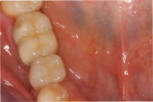

Mikrochirurgischer Wundverschluss

Gingivatransplantat fixiert

Zustand 3 Wochen post OP